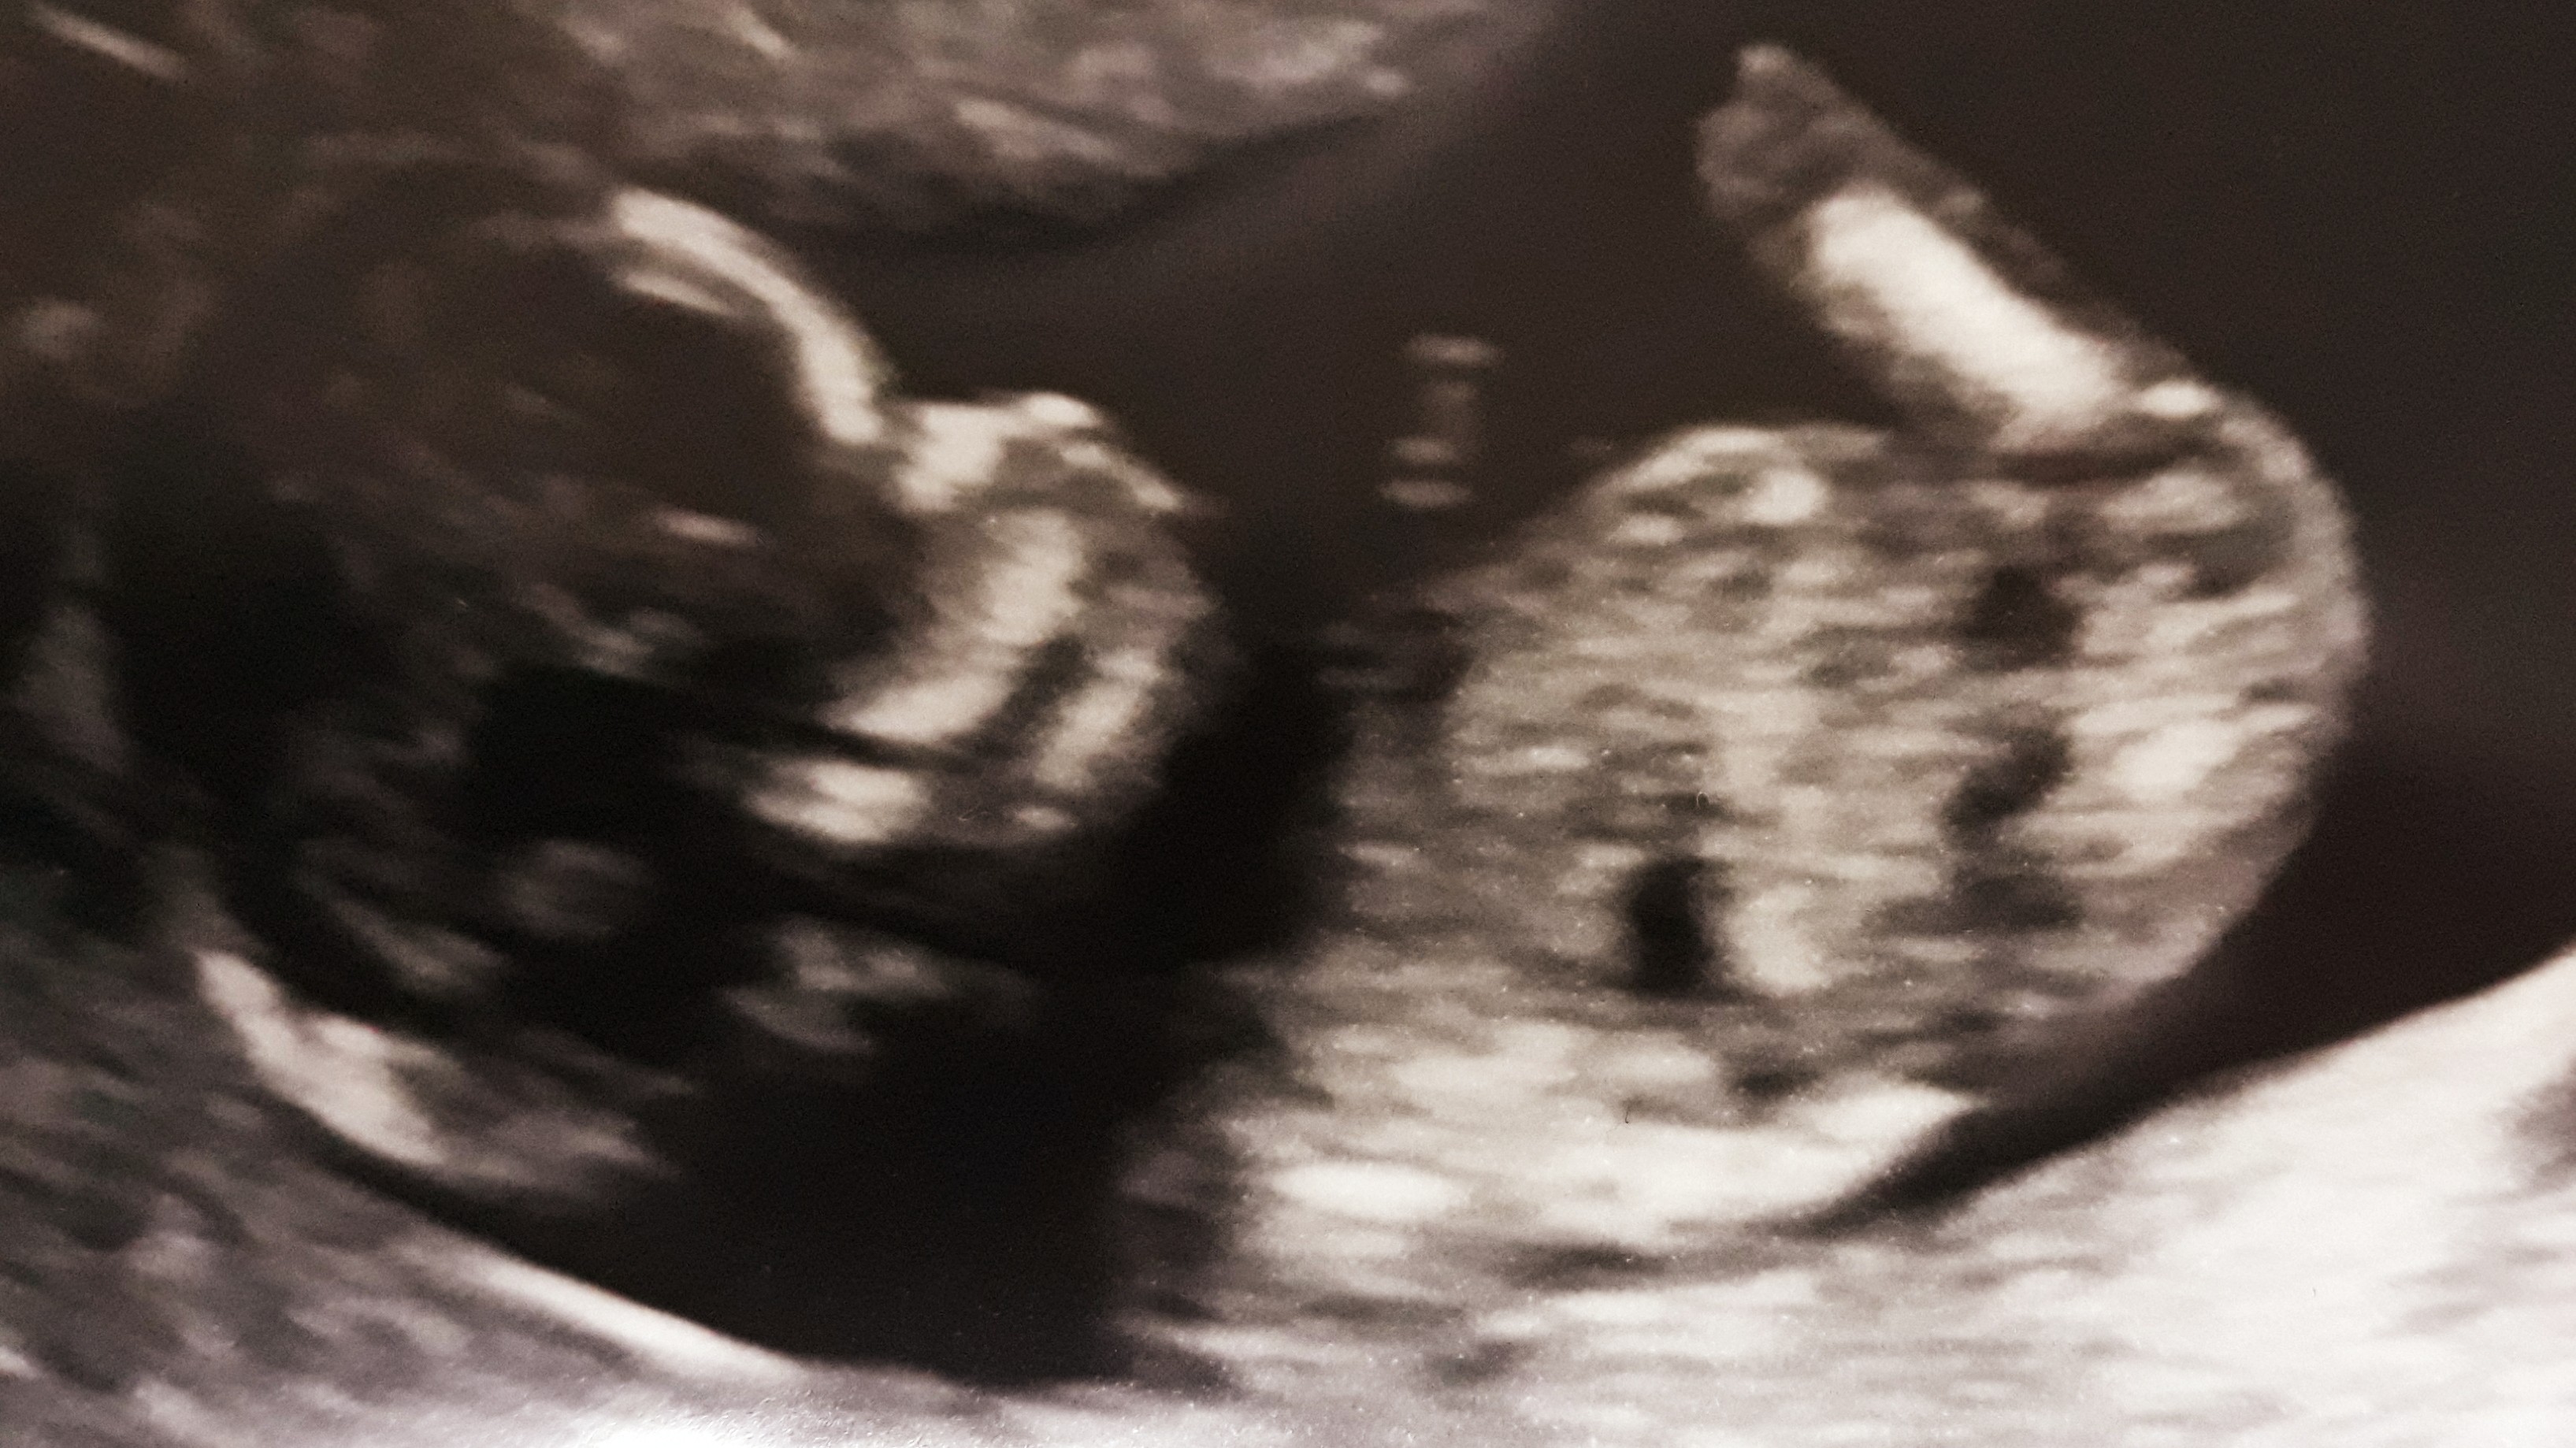

. My nie musieliśmy nic mówić, zadawać pytań, ponieważ lekarz był naprawdę konkretny i wyczerpująco opowiadał. Dziecko ma 6 cm, prawdopodobnie jest to córka, ale na tym etapie zdarzają się pomyłki, więc nie nakręcamy się. Pokazywał nam rączki, nóżki, kręgosłup, żołądek, pęcherz, serce. Prawie 160 uderzeń na minutę - musiałabym sprawdzić, bo nie pamiętam dokładnie czy 156 czy 159. Słyszeliśmy serduszko. Wyniki PAPPA będą za jakieś 2 tygodnie.

Zobacz załącznik 901374 Zobacz załącznik 901373